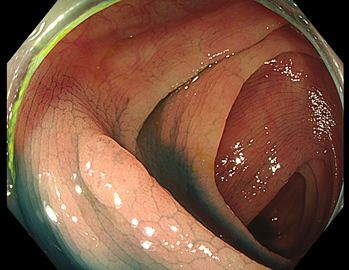

TXIは、「画像の構造を強調する」技術です。これは特別に目新しいものではありません。パソコンの画像編集ソフトや、スマホのアプリでも御馴染みの技術です。しかし、「どのような構造強調が実際に、内視鏡に一番、合うか?(強すぎると不自然になる!)」は、難しい(アナログ的な)課題です。オリンパス社は数タイプのTXIモードを用意しました。半年間の試行錯誤の末、今では下記のモードがベストと判断しました。そして今では「TXI無しの内視鏡は不要(フルタイムTXI)」というまで常用しています。

以下に実例を挙げます

写真だけ、見ると「言われてみるとTXIの方が認識しやすい。でも僅かの差」と感じるでしょうが、この「僅かの差」が、人間の脳での検出には大きな差になります。青い色素(インジゴ・カルミン)が非常に強調され、粘膜の凸凹が明瞭になるのが特徴です。

通常観察 TXIモード